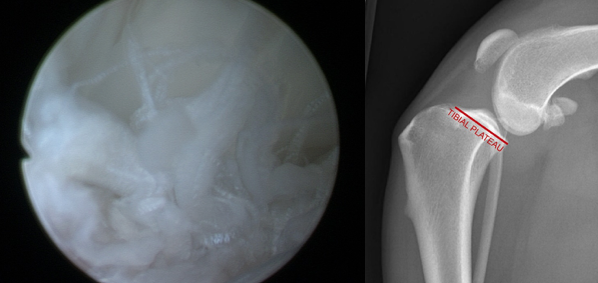

The cranial cruciate ligament is in the dog’s knee. The image on the left shows how the CCL is oriented in order to prevent the femur from sliding off the back of the tibia. The image in the middle shows where the CCL is located inside the canine knee as you look at the knee from the front view. The image on the R is an arthroscopic image looking inside a dog’s knee and showing an intact (i.e. normal) CCL. It is big, strong, smooth, white structure providing knee stability.

The image to the left is an arthroscopic image looking at a dog’s ruptured (torn) cranial cruciate ligament. It looks like the ends of a mop. On the right we can see that the femur is sliding off the back of the tibia, which is why procedures like TPLO surgery (aka “dog ACL surgery”) are necessary to stabilize the knee after a CCL rupture.